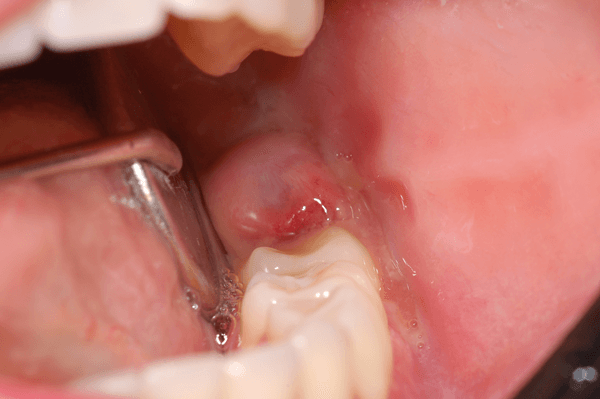

Pericoronarite

A inflamação dos tecidos ao redor de um dente em erupção, especialmente terceiros molares, pode causar dor intensa, edema e limitação de abertura bucal.

O tratamento pode envolver irrigação local, antibioticoterapia e, em casos recorrentes, extração do dente impactado.

(Reprodução/ImplantNews)